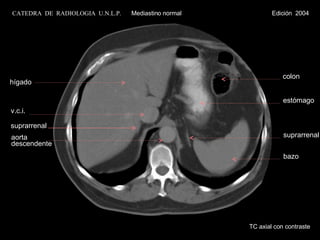

TC axial con contraste hígado v.c.i. suprarrenal bazo suprarrenal estómago colon aorta descendente CATEDRA  DE  RADIOLOGIA  U.N.L.P.   Mediastino normal  Edición  2004

suprarrenal TC axialcon contraste hígado v.c.i. espacio retrocrural colon estómago bazo aorta descendente CATEDRA DE RADIOLOGIA U.N.L.P. Mediastino normal Edición 2004

TC axial concontraste hígado v.c.i. suprarrenal bazo suprarrenal estómago colon aorta descendente CATEDRA DE RADIOLOGIA U.N.L.P. Mediastino normal Edición 2004